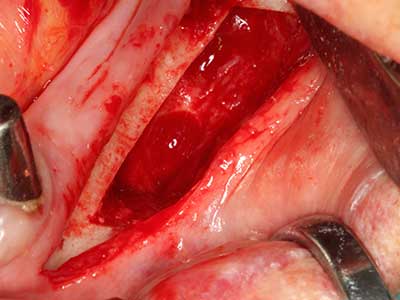

Indication: Apical resection

When surgical procedures are performed on bone in the immediate vicinity of sensitive structures such as blood vessels or nerves, rotary instruments pose a significant risk of iatrogenic injury. Piezoelectric devices can be helpful for preparation of bone covers and removal of hard tissue close to nerves, particularly for exposure of nerves after iatrogenic injury but also during nerve lateralization for resective and reconstructive procedures or implant placement (Fig. 17-20). Light contact between the piezotip and the nerve does not generally result in damage but proceeding incautiously with saw-like motions or attachments where a residual bone substrate remains may cause temporary or even permanent nerve damage. However, the risk of damage is considered to be substantially lower than when using saws or milling instruments (Pereira, Gealh et al. 2014).